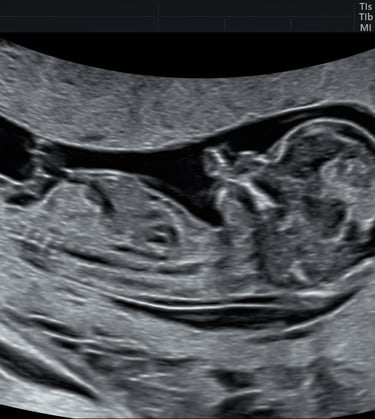

L’échographie du 2ème trimestre

(dite morphologique)

L’échographie morphologique doit être réalisée entre 21 SA et 24 SA. Elle permet de vérifier la bonne vitalité du fœtus, de réaliser une morphologie complète, de déterminer la croissance et la localisation placentaire.